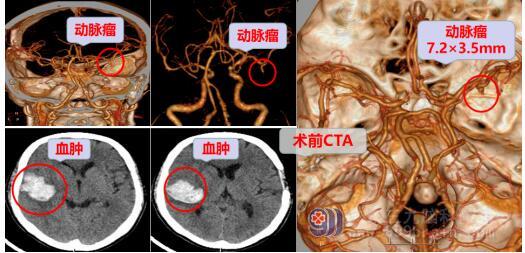

61岁的蔡叔在3天前出现头晕伴说话不清、手脚无力,到当地卫生院就诊时出现左侧肢体乏力、嘴角歪斜,急送当地医院,行头部CT检查右侧颞叶出血,CTA可疑为右侧大脑中动脉分支动脉瘤。家属为求进一步治疗,辗转来到广东三九脑科医院神经外十科。

蔡叔入院后完善了相关检查,神经外十科主任欧阳辉教授结合蔡叔的头颅CT/MR/DSA结果考虑为右侧大脑中动脉分支动脉瘤。颅内动脉瘤被称为“不定时炸弹”,是造成蛛网膜下腔出血的首位病因,动脉瘤一旦爆裂,致死率和致残率极高,所以必须尽快手术治疗。